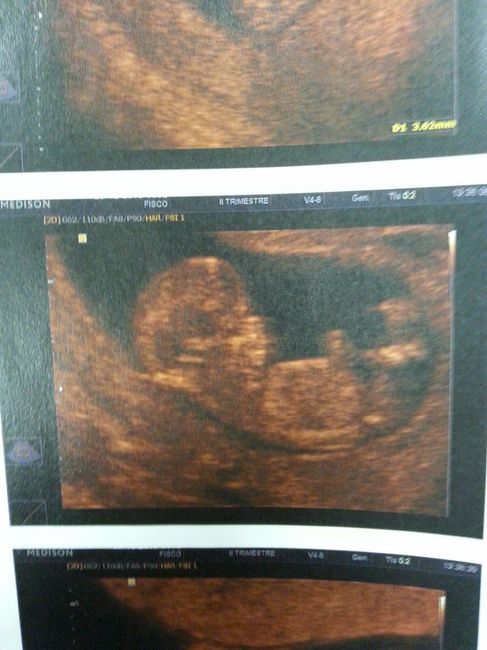

Ciao a tutte belle mammine Mi è venuta un'idea.. Cosa ne dite di condividere in questo topic la foto del profilo ecografico dei nostri fagottini ogni qualvolta andiamo a fare un'ecografia ? Magari scrivendo la settimana di gravidanza, nome...